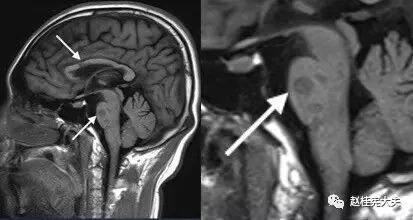

图4. 示T1矢状位像,胼胝体上缘可见多发斑片状低信号,“Dawnsing finger“即“指压征”。

图7. 矢状位T1像示:胼胝体深部、侧脑室上缘,脑桥见多发斑片状低信号。